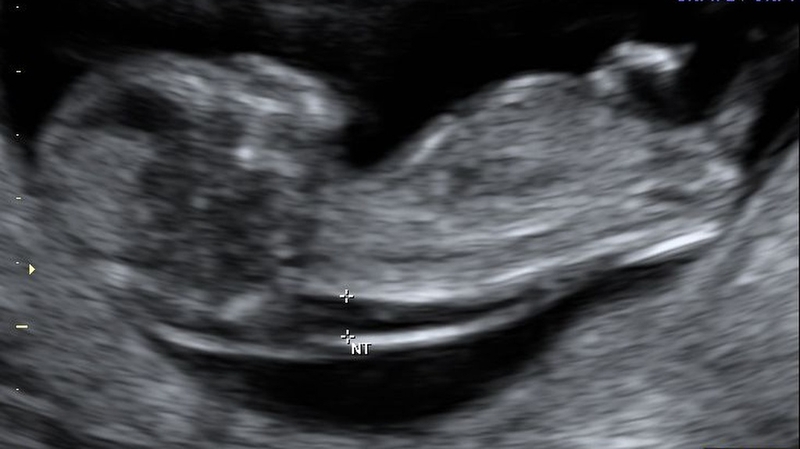

Độ mờ da gáy (có tên tiếng Anh là Nuchal Translucency) là thuật ngữ dùng để mô tả khoảng tích tụ dịch ở dưới da phía sau gáy của thai nhi trong tam cá nguyệt đầu tiên. Nó thường xuất hiện dưới dạng một vùng mờ trên màn hình siêu âm và được đo trong giai đoạn từ 11 - 13 tuần tuổi hoặc khi thai nhi có kích thước đầu mông từ 45 - 84 mm. Mặc dù mọi thai nhi khỏe mạnh đều có lớp chất lỏng này phía sau gáy, nhưng khi bị mắc hội chứng Down hoặc những bất thường khác về nhiễm sắc thể thì lớp chất lỏng này sẽ dày hơn so với mức bình thường. Do đó, việc đo độ mờ da gáy có thể giúp phát hiện sớm các vấn đề này.

Thông thường, những thai nhi có kích thước đầu và mông từ 45 - 84 mm sẽ có độ mờ da gáy tiêu chuẩn dưới 3.5 mm.

Khi độ mờ da gáy nằm trong khoảng từ 3.2 - 3.5 mm, trẻ có nguy cơ nhiễm sắc thể đột biến khá cao. Do vậy, bác sĩ có thể sẽ khuyến nghị mẹ bầu thực hiện thêm một số xét nghiệm chuyên sâu để an tâm hơn về tình trạng sức khỏe của thai nhi.